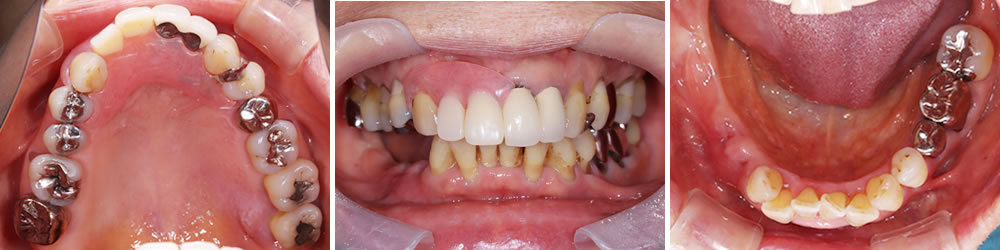

こちらの患者さまは、右下奥欠損部へ歯を入れたいとの主訴で来院されました。来院1ヵ月前に他院にて右下奥歯を2本抜歯したとのことでした。

義歯やインプラントといった方法があり、メリットデメリットを説明したところ、今回はインプラントによる治療を希望されました。

また、口腔内全体の状態を確認すると、右上奥歯の挺出(下方に伸びている状態)も認めたため、上下でバランスをとって補綴する計画を立てました。

治療前後の比較

インプラント治療により、固いものもしっかり噛めるようになったとのことでした。また、歯肉移植を併用したことで、インプラント周囲の清掃性も向上しました。